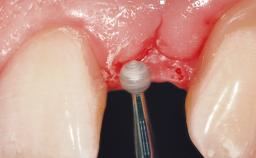

Immediate Flapless Placement of an Implant in a Maxillary Left Central Incisor Site

A 42-year-old female patient was referred to our clinic at the School of Dentistry of the University of São Paulo in November 2004, presenting a deficient restoration in the upper left central incisor. The clinical examination revealed no gingival retraction or any signs of gingival inflammation and, therefore, previous periodontal treatment was not considered. The patient presented a high lip line at full smile and a thin tissue biotype. This combination characterized a high-risk situation from an anatomic point of view, which required careful preoperative planning and cautious surgical execution.

Loading Protocol Immediate

Provisional Implant-Supported Prosthesis Prosthodontic margin < 3 mm apical to mucosal margin Prosthodontic margin < 3 mm apical to mucosal margin